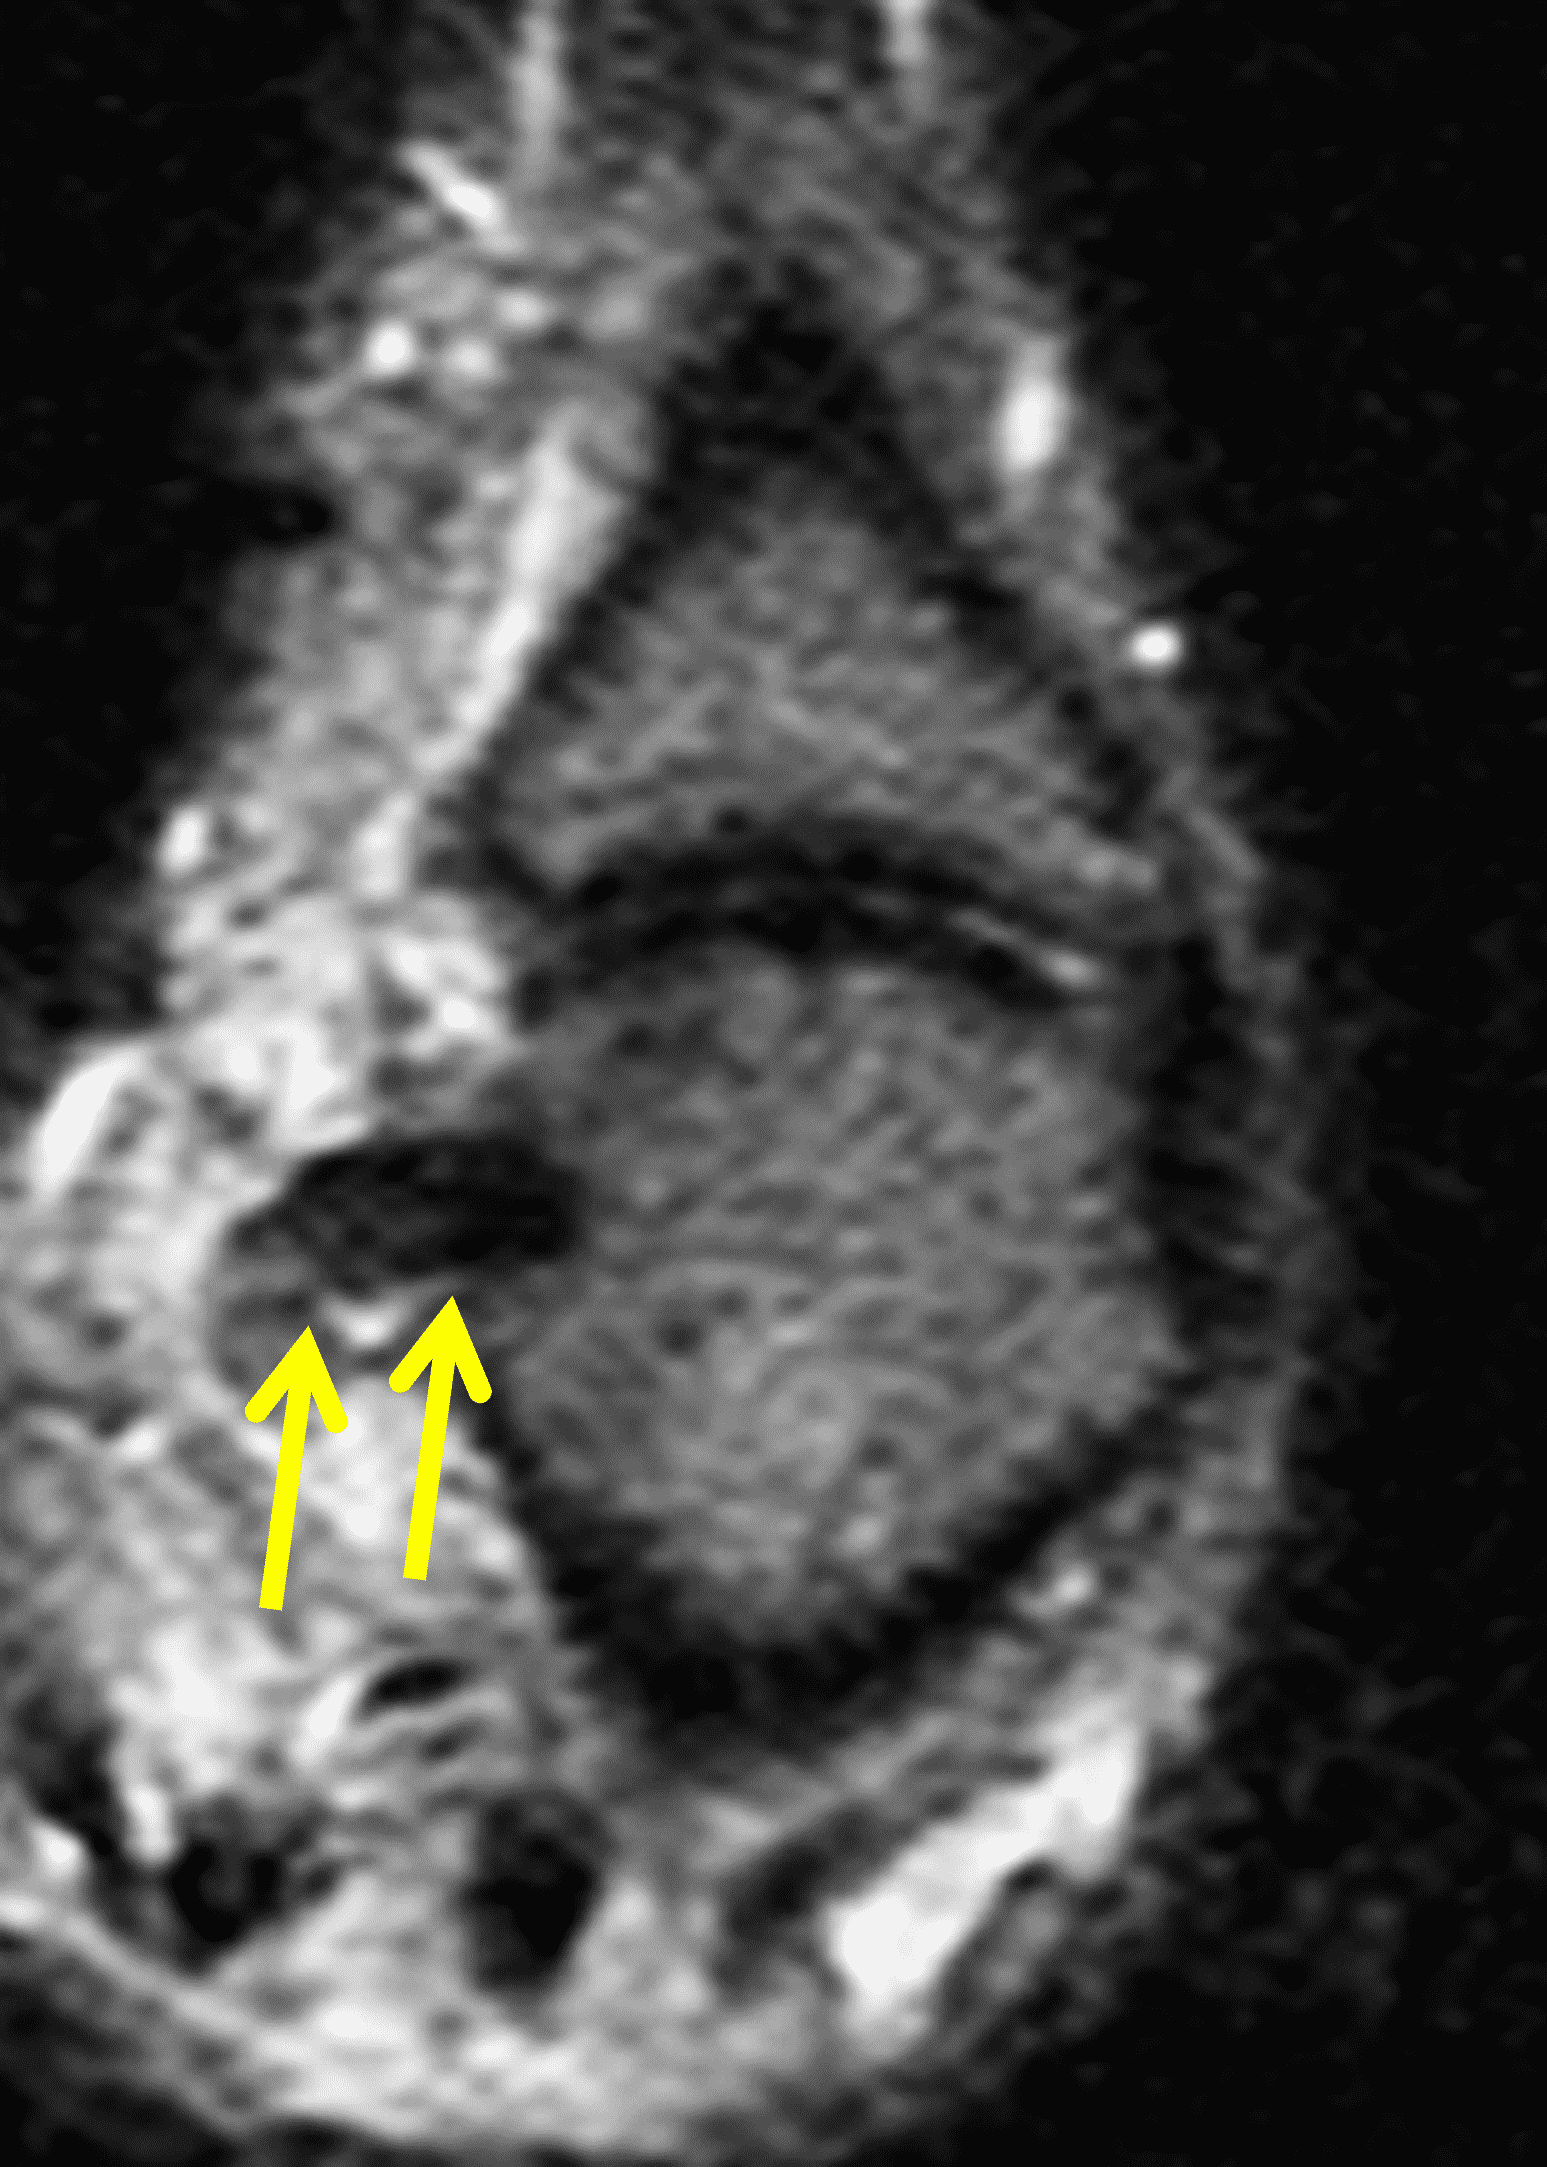

A 30-year-old male presents with pain at the metacarpophalangeal (MP) joint of the thumb following a bicycle wreck. Coronal proton density-weighted (Figure 1A) and inversion recovery (Figure 1B) images, and consecutive axial proton density-weighted images (Figure 1C and 1D) are provided. What are the findings? What is your diagnosis?

Figure 2: The coronal images (2A and 2B) reveal a complete tear of the thumb MP joint ulnar collateral ligament (UCL) from its distal insertion. The torn ligament (arrows) is retracted proximal to the adductor aponeurosis (arrowhead), best seen on the proton density-weighted sequence, and the torn ligament points ulnarly rather than distally. The adductor aponeurosis (arrowheads) is fully visualized in the axial plane at the metacarpal head (2C). An axial slice (2D) just proximal the aponeurosis reveals the balled-up, retracted UCL (arrow).

Complete distal disruption of the ulnar collateral ligament at the MP joint of the thumb, with a Stener lesion.